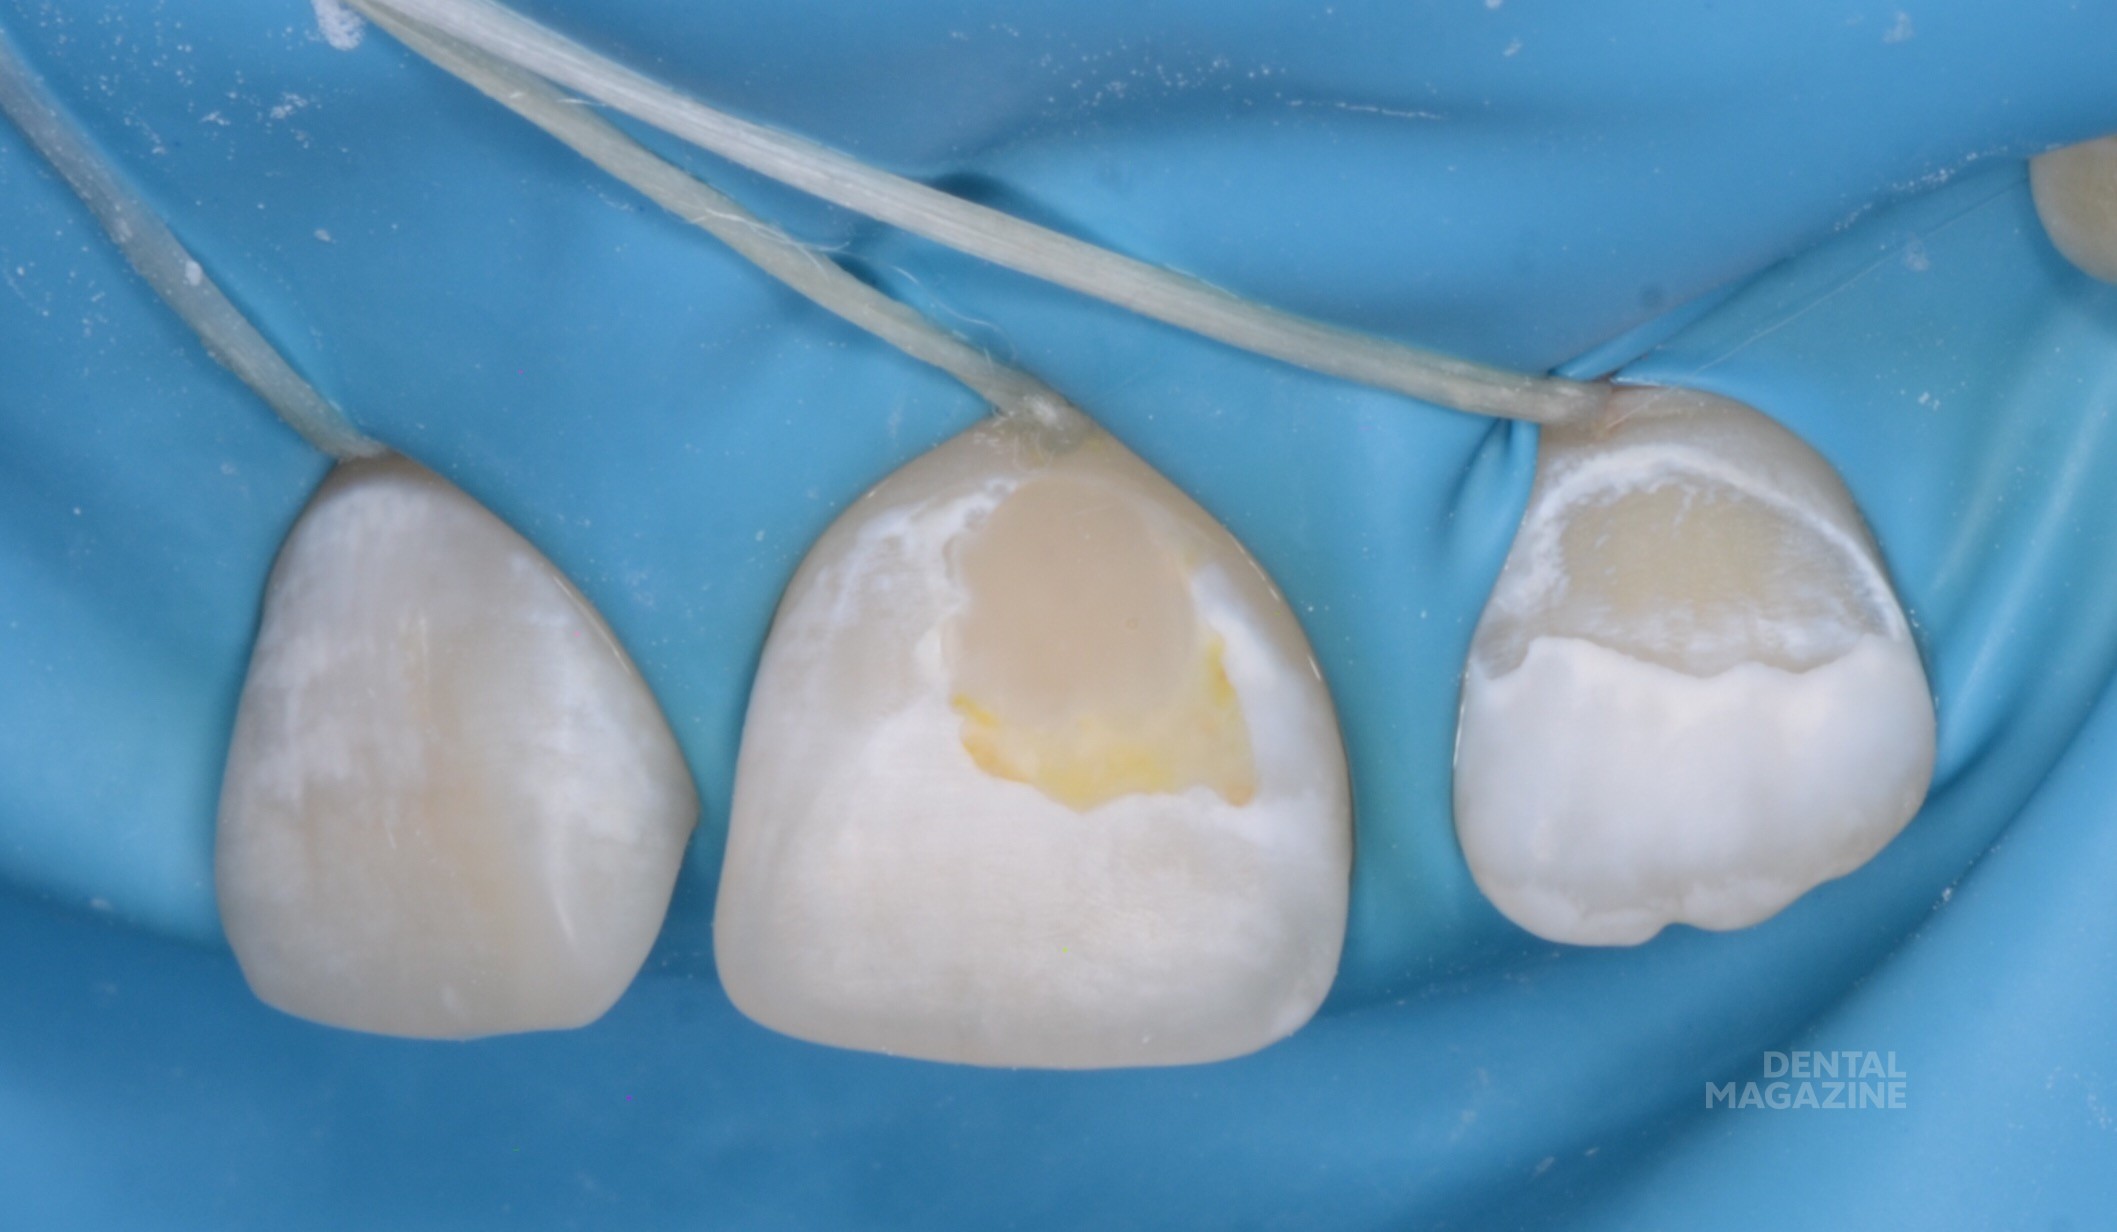

Иллюстрации флюороза молочных зубов

Раздел: Необычные решения